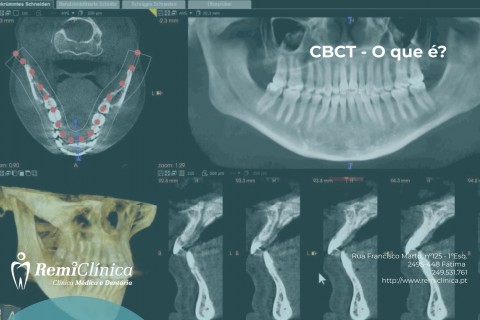

CBCT - O que é?

As imagens obtidas permitem planear cirurgias de forma minimamente invasiva...